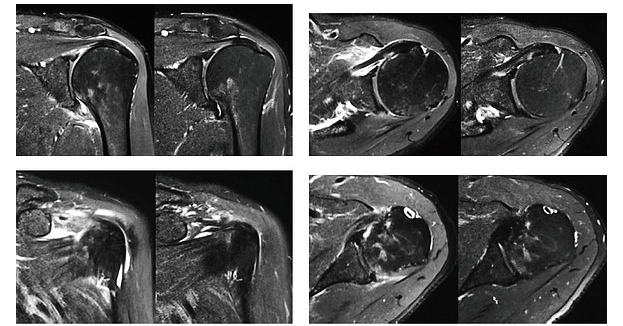

裁断済み】 肩関節のMRI 第3版 - 健康・医学 - 健康・医学。肩関節のMRI−読影ポイントと新しい知見−第3版 | 佐志 隆士。春日クリニック】MRI画像で見る肩関節 - YouTube。Kokuu グルテンフリー雑穀300g2袋。第42回日本磁気共鳴医学会大会/肩関節腱板の小さな断裂の診断。m3電子書籍 | 肩関節のMRI 第3版。腱板断裂【肩関節外科】 | おおさかグローバル整形外科病院。傷、折れなど細かな破損を気にされる方はご遠慮下さい。凍結肩の MRI所見 : 整形外科医のブログ。その腱板断裂、ホントに交通事故の後遺症?:日経メディカル。肩関節脱臼|SPORTS MEDICINE LIBRARY|ザムスト(ZAMST)。右肩腱板断裂 いしもと整形外科リハビリクリニック - 【公式。裁断済みの為全体的に状態が悪いとしてあります。素人目での判断ですが、スキャンして使用する分には問題ありません。肩関節疾患について(2)~治療方針~ - 医療法人相生会 福岡。その他検査(関節・軟骨) 肩MRI | AIC八重洲クリニック。書き込み、マーカーはありません。